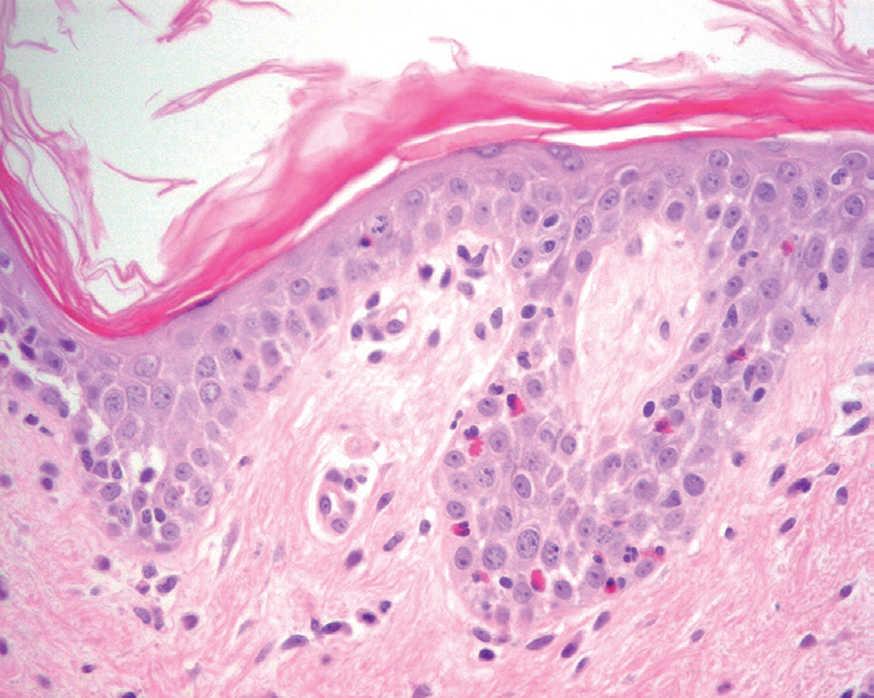

Más infrecuentes el hallazgo histopatológico inicial es una espongiosis eosinofílica (fig. 20) y neutrofílica, a veces en la misma biopsia. La hendidura puede afectar no sólo a la epidermis, sino también a los anejos, de manera que se puede observar en la totalidad del folículo terminal. También pueden encontrarse implicadas la glándula sudorípara y la glándula sebácea.

Fig. 20.--Espongiosis eosinofílica.